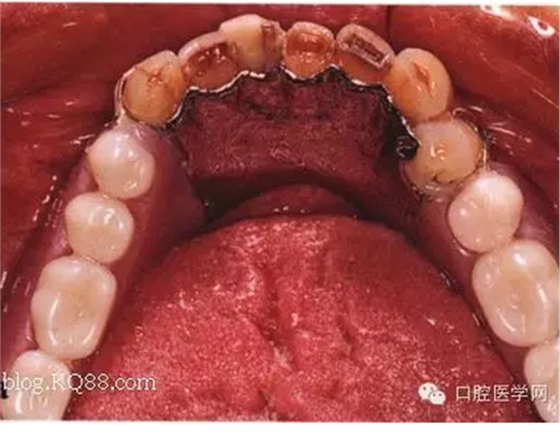

先注明一下:本文圖片部分來自李望松的支架設(shè)計(jì)圖譜收集u/210/archives/2008/25181.html,借圖表達(dá)一下,沒有別的目的,只是讓文章更生動(dòng)些,李老師一直是我崇拜的偶像,只是近來很少見到他的文章,期待李老師的大作,言歸正傳——————修復(fù)大夫要精通支架設(shè)計(jì),作為一個(gè)修復(fù)大夫,是第一個(gè)獲得患者牙體狀況的,所以說在哪放個(gè)合支拖,在哪放個(gè)卡換,至關(guān)重要,因?yàn)槲覀冏龅氖莻€(gè)有創(chuàng)不可逆操作,既要兼顧牙周狀況,又要兼顧粘膜狀況,以及牙槽脊的情況,所以說當(dāng)給患者做完檢查以后我們頭腦中就應(yīng)該有一個(gè)大體支架了,以前,總是太依賴加工廠了,取完模剩下的好像都是交給了加工廠了,怎么設(shè)計(jì),你看摸著辦吧,仿佛設(shè)計(jì)那是加工廠的事,可是做了幾回再加上自己的學(xué)習(xí),經(jīng)驗(yàn),加工廠的設(shè)計(jì)總是不怎么樣,以前設(shè)計(jì)的方案仿佛根深蒂固,一直就認(rèn)為那是正確的就那么設(shè)計(jì),再加上以前看過支抗兄的一篇文章,也是深有感觸,一個(gè)不科學(xué)的設(shè)計(jì)方案,那樣就成了一個(gè)慢性拔牙器??纯磶追鶊D片

看紅箭頭處為什么要空出一點(diǎn)距離?,看看自己加工廠設(shè)計(jì)的不管牙怎樣是不是都成了一個(gè)整體呢?對(duì)于愕板或者是